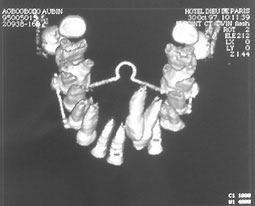

Le Scanner :

Le scanner est une chaîne radiologique tomographique assistée d’un ordinateur qui mesure les densités d’un objet anatomique avec une reconstruction matricielle d’une image numérisée, visualisée selon différents contrastes.

Le scanner est de loin la technique de localisation la plus précise. Il permet non seulement une localisation précise des inclusions mais détermine également les rapports avec les dents et les structures voisines de même que leur état parodontal (ankylosées ou pas).(fig 9, 10).